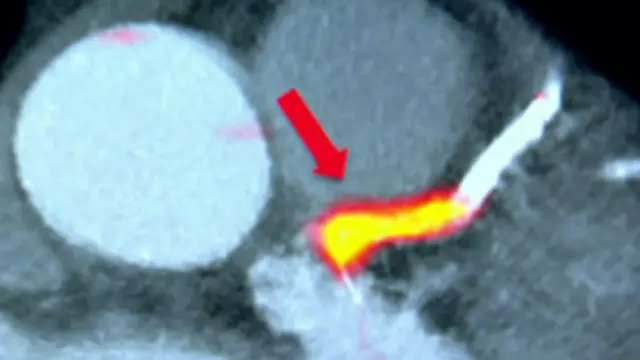

محققین نے مریضوں کے جسموں میں ایک تابکار سیال مادہ داخل کیا جو چربی کے خطرناک لوتھڑوں سے چمٹ جاتا ہے۔ اس کے علاوہ دل اور شریانوں کی ہائی ریزولیوشن تصاویر بھی لی گئیں۔

ان دونوں تکنیکوں کا حتمی نتیجہ ایک تصویر کی شکل میں سامنے آیا جس میں شریانوں کے اندر خطرناک لوتھڑے واضح طور پر دکھائی دینے لگے۔